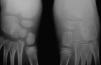

Prácticamente todas las enfermedades inflamatorias con posibilidad de cursar con manifestaciones articulares pueden producir artritis en las articulaciones del pie. El paciente pediátrico no es una excepción en cuanto a las manifestaciones inflamatorias en las estructuras articulares y tendinosas del pie pero, a diferencia del adulto, la artritis se produce en una fase en la que todavía no ha finalizado el desarrollo de los núcleos de osificación en las epífisis de los huesos largos y en los huesos cortos; esta circunstancia hace que la inflamación articular en la infancia tenga sus peculiaridades1,2. La hipervascularización, que acompaña al proceso inflamatorio, hace que se produzca un desarrollo acelerado de la osificación, muy evidente en casos de afección unilateral (fig. 1), que puede dar lugar a variaciones en el tamaño de los núcleos de osificación o incluso en su morfología provocándose el consiguiente trastorno funcional.

Figura 1. Forma oligoarticular extendida. Aceleración de la osificación de los huesos del tarso del pie izquierdo como consecuencia de la tarsitis.